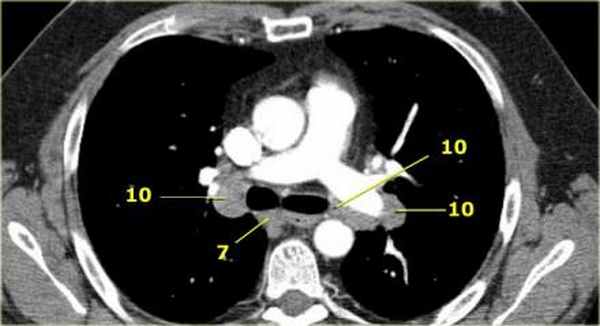

7. Подкаринальные лимфатические узлы

Эти лимфатические узлы расположены ниже уровня бифуркации трахеи (карины), но не относятся к нижнедолевым бронху и артерии. Справа они располагаются каудальнее нижней стенки промежуточного бронха. Слева они располагаются каудальнее верхней стенки нижнедолевого бронха.

Слева лимфатический узел 7 группы справа от пищевода.

10. лимфатические узлы корня легкого

Лимфатические узлы корня расположены проксимальнее долевых узлов, но дистальнее медиастинальной дупликатуры и узлов промежуточного бронха справа.

Все лимфатические узлы 10-14 групп являются N1 узлами, так как они находятся вне средостения.